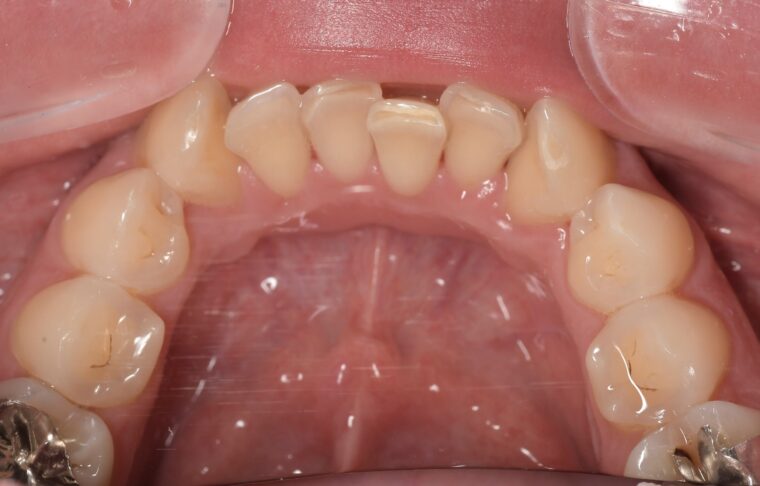

Before

After

基本情報

| 主訴 | 見た目をきれいにしたい |

| 治療期間 | 6ヶ月 |

| 治療費 | ジルコニアボンド(セラミックの被せもの)¥165,000×7(税込み) オフィスホワイトニング4回 ¥4,400×4(税込み) ホームホワイトニング¥11,000 |

| リスク・副作用 | かみ合わせがとても強い方の場合、稀に割れてしまうことがあります。 |

| 先生からの提案 | 上の前歯6本と右下の2番目の歯はセラミックの被せもので治療。 残りの下の前歯5本はプラスチックの材料で虫歯を治療し、 ホワイトニングをおこないました。白くなったご自身の歯の色に合わせてセラミックの 被せものを作成しています。 模型上で完成後をシュミレーションし、上の歯茎の位置をきれいに見えるように 揃えています。(外科処置はしていません) |